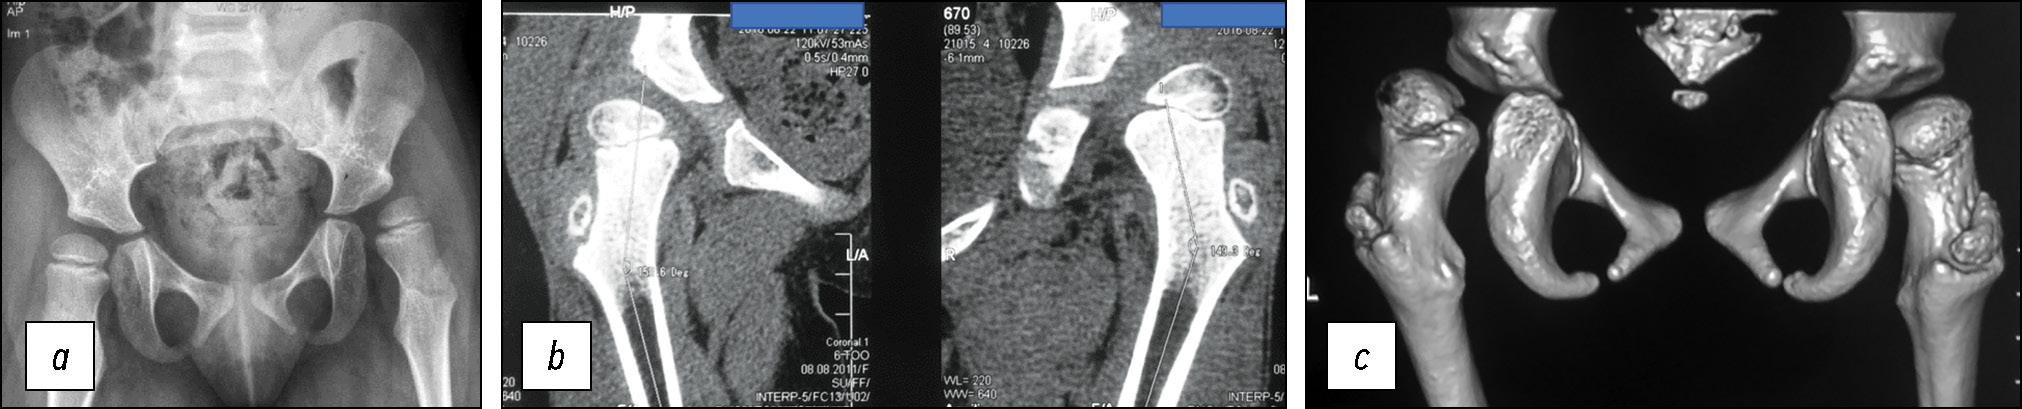

Рис. 2. Рентгенограмма таза и компьютерная томограмма пациентки В. до лечения: a — рентгенограмма таза, индекс Reimers 26% (справа), 68% (слева); АИ 23° (справа), 31° (слева); b — фронтальный АИ, 27° (справа), 39° (слева); c — 3D-реконструкция (вид сзади), иллюстрирующая преимущественно заднелатеральную локализацию ацетабулярной дисплазии. АИ — ацетабулярный индекс.

Fig. 2. X-ray of the pelvis and computed tomogram of patient V. before treatment: a — X-ray of the pelvis, Reimers index 26% (right), 68% (left); AI 23° (right), 31° (left); b — frontal AI, 27° (right), 39° (left); c — 3D reconstruction (posterior view), illustrating the predominantly posterolateral localization of acetabular dysplasia. АI — acetabular index.